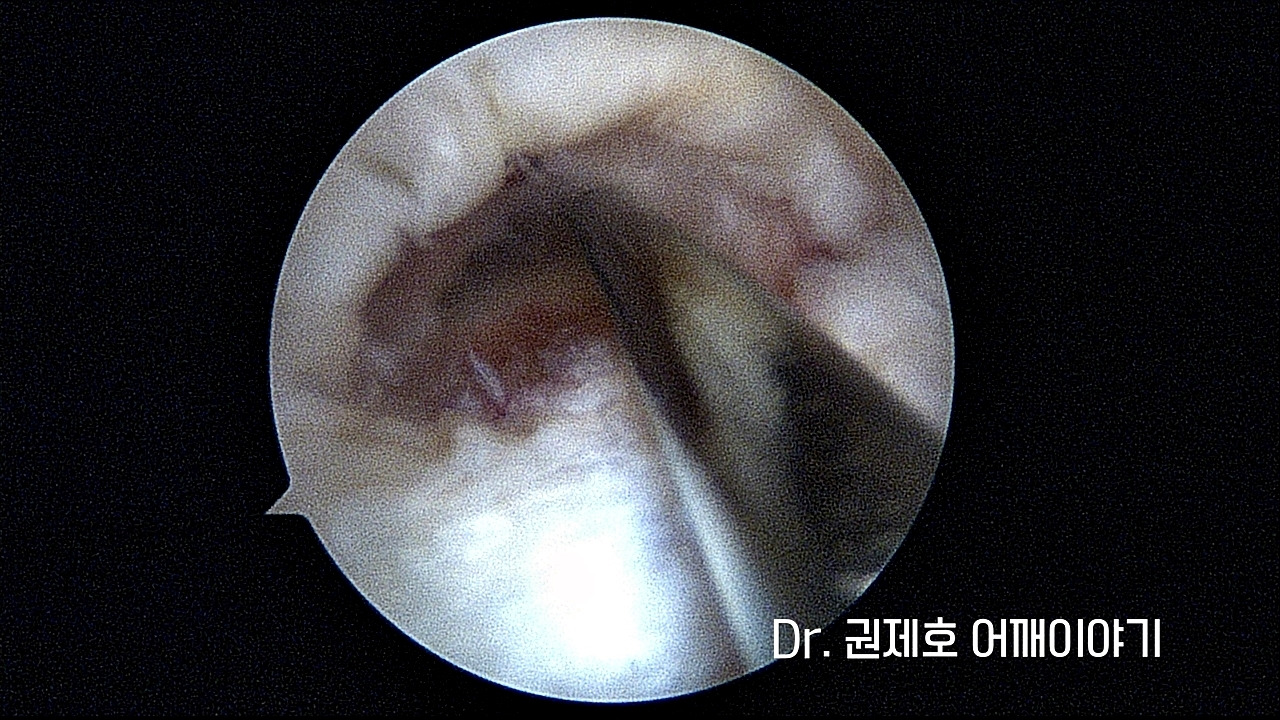

위에서 언급하였듯이 어깨 회전근개파열이 완전 파열이었기에 수술적 치료로 결정했습니다. 관절경 사진으로 보면 회전근파열이 명확하게 관찰됩니다.